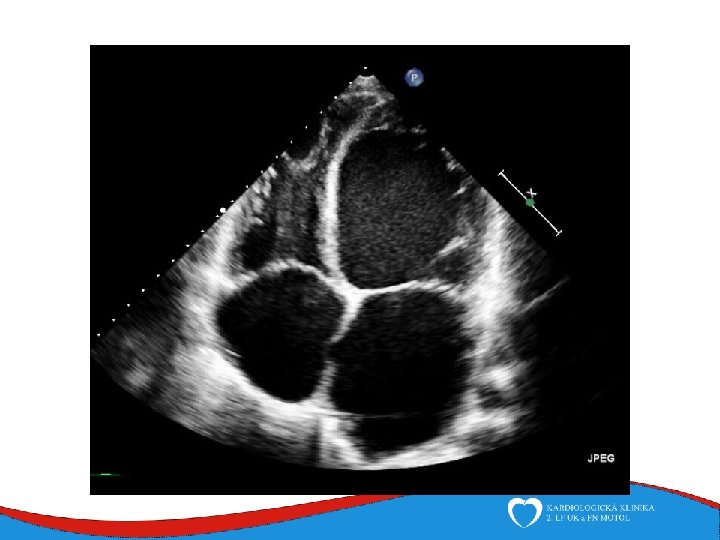

ECHO – anterior wall akinesis, LV EF 35%, mild mitral regurgitation, no dilation of right-sided chambers, no pericardial effusion